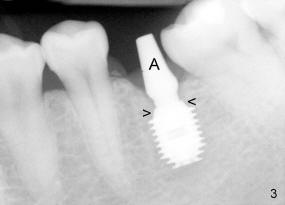

The tooth #19 has been lost for 8 years with tilting of #18 (black line in Fig.1). A 6x8 mm Bicon implant (3 mm post) was placed as distal as possible (I in Fig.2). Three months later, the implant was uncovered with evidence of osteointegration (arrowheads in Fig.3). A 4x6.5 mm 0 degree non-shouldered abutment with 3 mm post (A) was inserted into the implant well. The flat surface of the abutment needed to face distal in order to seat the abutment without interference. The implant/abutment complex was used as an anchorage to upright #18. The tooth #17 was extracted prior to orthodontic treatment (compare Fig.5,6 vs. 1-3). A bracket was bonded to Jet temporary crown of #19 and open coil spring was placed between #18 and 19. In the first two months, distalization of #18 is limited (between black and white lines in Fig.4), partially due to the fact that the bracket of #19 was debonded quite easily. A premolar band (B in Fig.5) was cemented to the temporary crown of #19. In another two months, the tooth #18 was pushed to desired position (arrowhead) under the tension of open coil spring (*). The mesial crest height of #18 was increased during uprighting (arrow, as compared to Fig.1-3). A new temporary crown was fabricated to fit the enlarged space of #19 with cementation of a molar band. The next problem is that the new molar temporary crown was easily dislodged from the 4x6.5 mm abutment even with a permanent cement. A larger abutment (5x6.5 mm) was used (Fig.6), with relining the temporary crown. The upper end of the larger abutment has sharp edge (Fig.8: white arrowhead, as compared to rounded edge of the smaller abutment (Fig.7). This may also contribute to better retention. In another 3 months, the temporary crown was dislodged again. An even larger abutment (6.5x6.5 mm with two flat surfaces (blue arrowheads in Fig.9) was adopted.